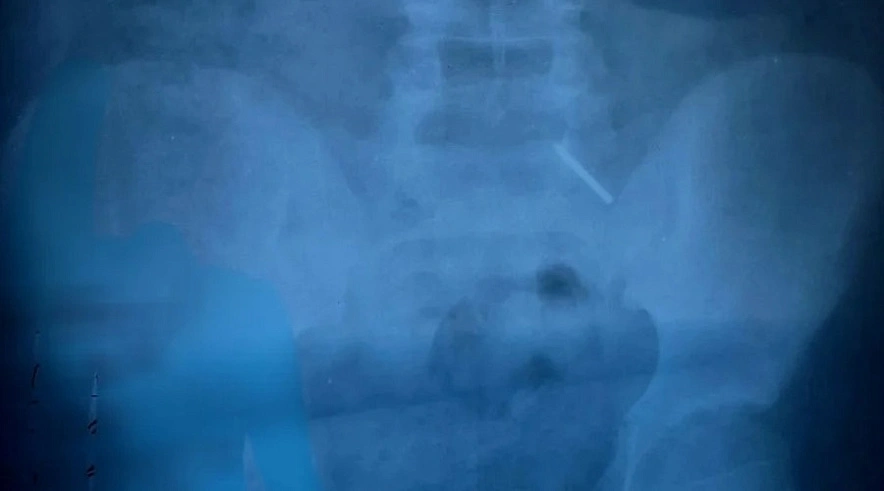

В балаковскую больницу привезли мальчика, который проглотил часть циркуля. Острый предмет мог грозить серьезным повреждением кишечника, и балаковским врачам пришлось спасать ребенка.

Как сообщает Балаковская городская клиническая больница (БГКБ), инородный предмет был обнаружен в желудке 11-летнего мальчика. По каким причинам ребенок проглотил часть циркуля, врачам выяснить так и не удалось. По словам детского хирурга Дарьи Гусевой, такие поступки обычно совершают дети младшего возраста, и такой случай в практике балаковских врачей был едва ли не единственным.

«Эндоскопически достать предмет не представлялось возможным из-за позднего обращения пациента. Главной задачей было не допустить перфорации кишечника и кровотечения - мальчик находился под наблюдением врачей и рентгенологов. В итоге инородное тело вышло естественным путем. Пациент выписан домой», - рассказали в БГКБ.